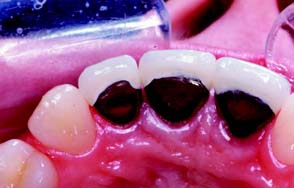

Not all ceramic crown preparations are conservative of tooth structure, as a wide 90-degree heavy chamfer margin must be prepared around the entire tooth to ensure increased material thickness and material strength. For the same reason, additional reduction on the lingual surface is needed for these restorations. A minimal material thickness of approximately 1 to 1.2 mm is necessary to ensure optimal esthetics. This limits the use of these restorations on faciolingually thin teeth and on teeth with large pulps, as in young individuals.

A compromised appearance of some metal-ceramic restorations (see Chapters 19 and 24) is often caused by insufficient porcelain thickness. On the other hand, adequate porcelain thickness is sometimes obtained at the expense of proper axial contour (such overcontoured restorations almost invariably lead to periodontal disease). In addition, the labial margin of a metal-ceramic crown is not always accurately placed. To correct all these deficiencies, certain principles are recommended during tooth preparation that ensure sufficient room for porcelain and accurate placement of the margins. Otherwise, good appearance would be achievable only at the expense of periodontal health.

If there is to be sufficient bulk of porcelain for appearance and metal for strength, adequate reduction of the facial surface is essential. The exact amount of reduction depends to some extent on the physical properties of the alloy used for the substructure, as well as on the manufacturer and the shade of the porcelain. A good color match for some restorations in older individuals typically requires a slightly greater porcelain thickness than is needed in younger patients. A minimum reduction of 1.5 mm typically is required for optimal appearance. Adequate thickness of porcelain (Fig. 7-48) is needed to create a sense of color depth and translucency. Shade problems are frequently encountered in maxillary incisor crowns at the incisal and cervical thirds of the restoration, where direct light reflection from the opaque layer can make the restoration appear very noticeable. Because opaque porcelains generally have a shade different from that of body porcelains, they often need to be modified with special stains in these areas108 (see Chapter 24).